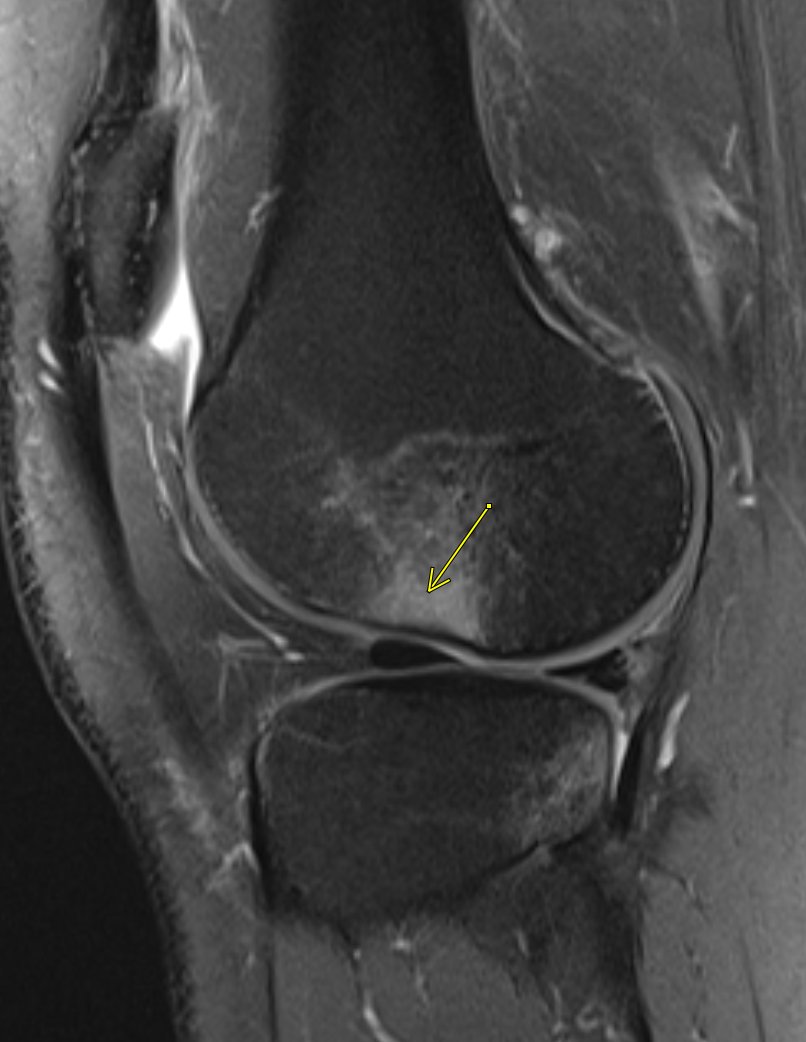

Occipital condyle avulsion fracture is often difficult to see on sagittal images

#radres always look on coronal and axial images, add this to your checklist#radiology#spine@NASSspine#EMRAd#FOAMed#spinetrauma#injurypic.twitter.com/lC7l73mnEj